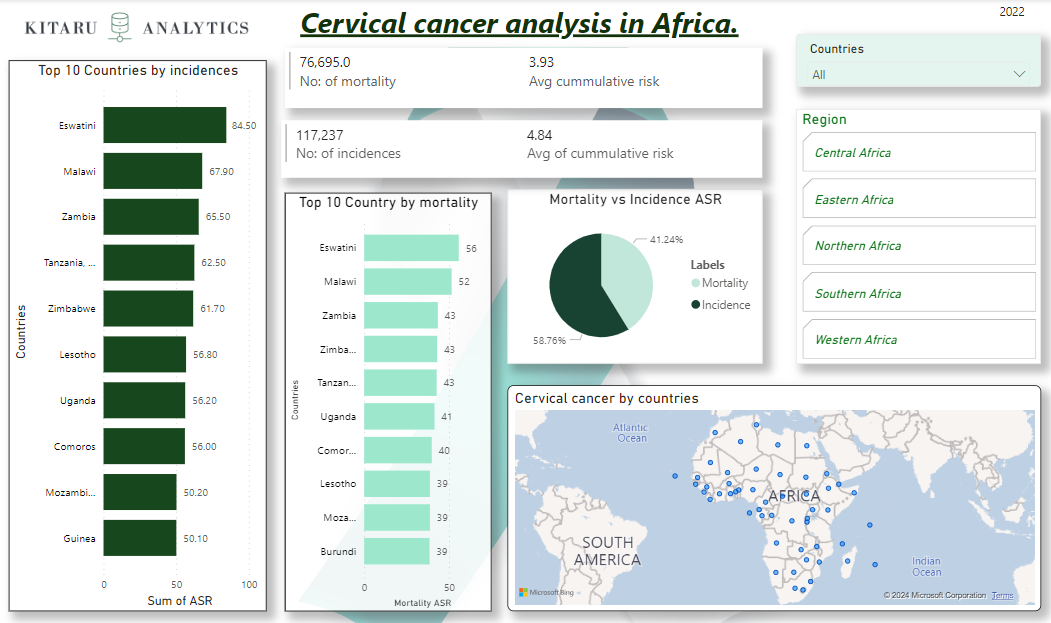

As January marks cervical cancer awareness month, it prompts a reflection of this common yet often misunderstood form of cancer. but what significance does this hold for Africa?